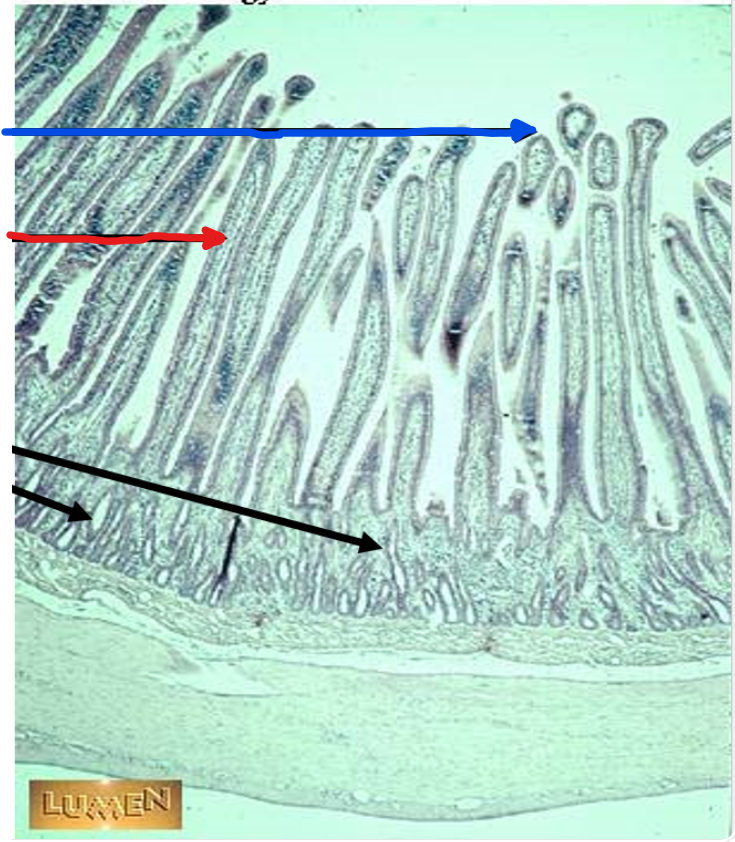

the blue arrow

villi

the red arrow

the black arrows

crypts

this is in the

jejunum

black arrows

mucosa

yellow arrow

submucosa

red arrows

muscularis externa

blue arrow

serosa